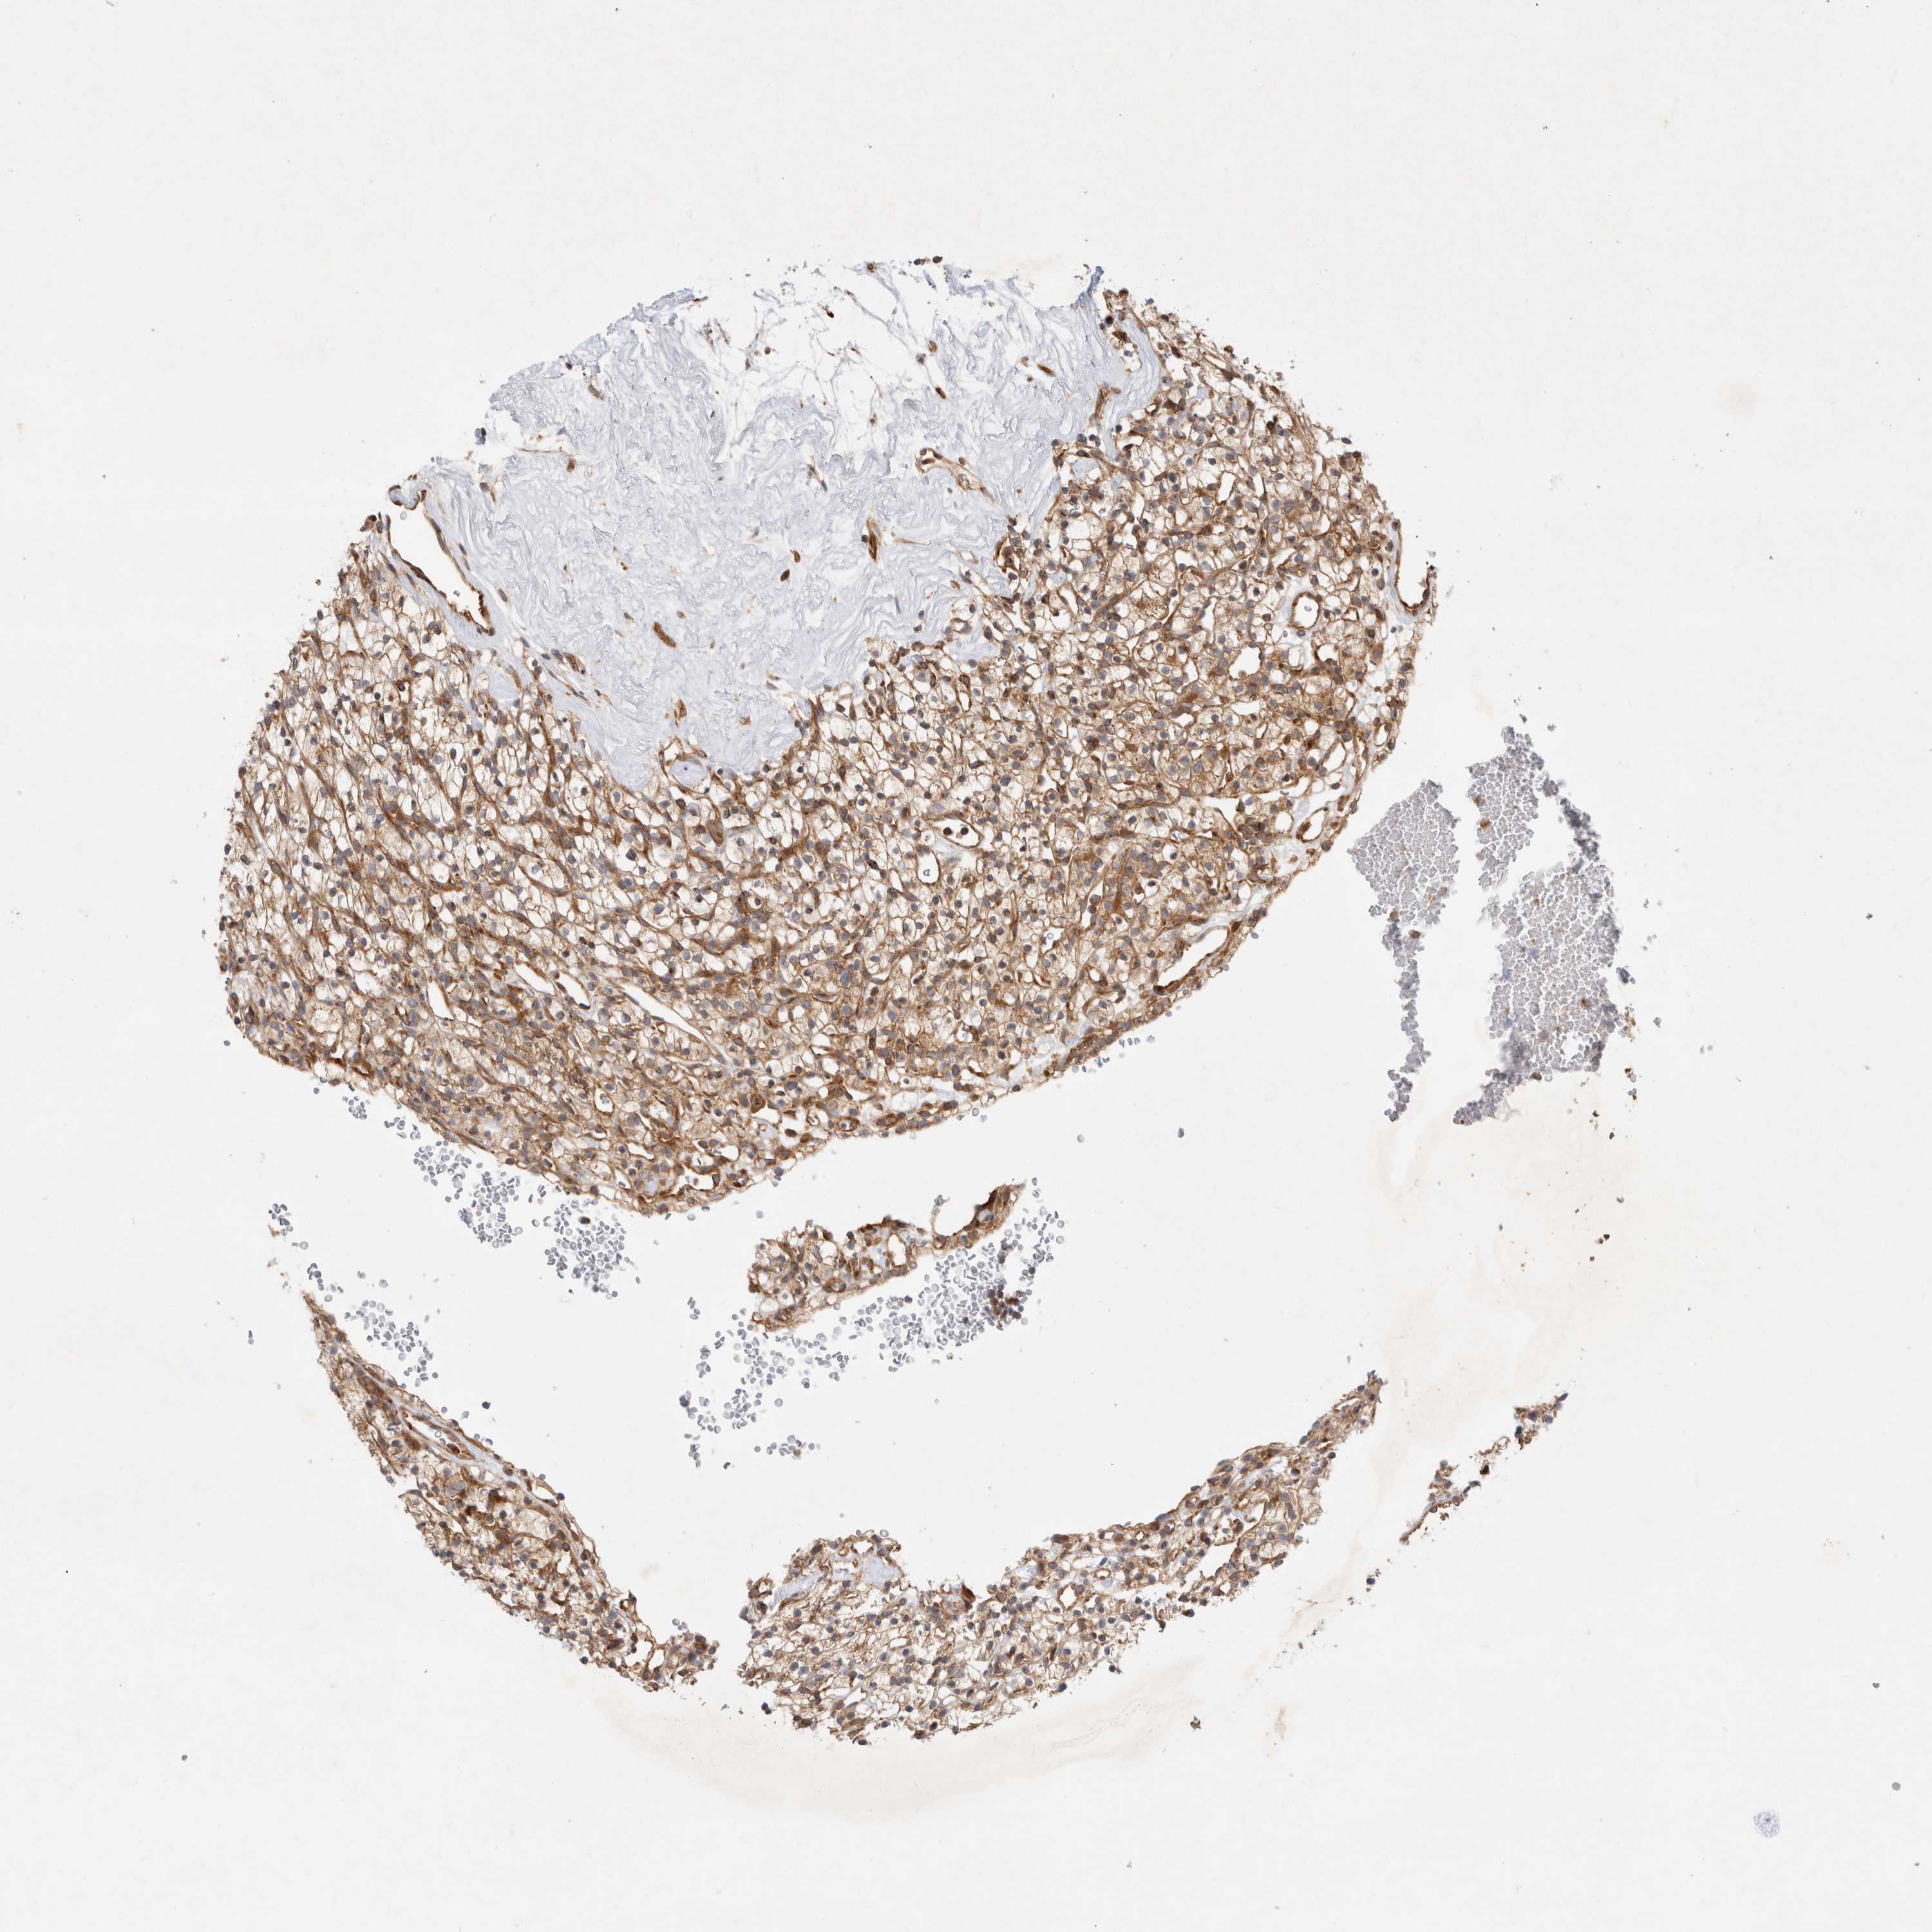

KIDNEY RENAL CLEAR CELL CARCINOMA (VALIDATION) - Interactive survival scatter ploti

The Survival Scatter plot shows the clinical status (i.e. dead or alive) for all individuals in the patient cohort, based on the same data that underlies the corresponding Kaplan-Meier plots. Patients that are alive at last time for follow-up are shown in blue and patients who have died during the study are shown in red.

The x-axis shows the expression levels (FPKM) of the investigated gene in the tumor tissue at the time of diagnosis. The y-axis shows the follow-up time after diagnosis (years). Both axes are complimented with kernel density curves demonstrating the data density over the axes. The top density plot shows the expression levels (FPKM) distribution among dead (red) and alive patients (blue). The right density plot shows the data density of the survived years of dead patients with high and low expression levels respectively, stratified using the cutoff indicated by the vertical dashed line through the Survival Scatter plot. This cutoff is automatically defined based on the FPKM cutoff that minimizes the p-score. The cutoff can be changed by dragging the vertical line or by entering a cutoff value in the square labeled "Current cut-off".

Under the Survival Scatter plot the p-score landscape (black curve; left axis) is shown together with dead median separation (red curve; right axis). Dead median separation is the difference in median mRNA expression between patients who have died with high and low expression, respectively. It is calculated as follows: median FPKM expression of dead patients with high expression - median FPKM expression of dead patients with low expression. This is intended to aid the user in visually exploring custom cutoffs and the associated p-scores and dead median separation.

Individual patient data is displayed and can be filtered by clicking on one or more of the category buttons on the top of the page. Categories describing expression level and patient information include: high, low, alive, dead, female, male and tumor stages. The scale of the x-axis can be toggled between linear and log-scale by clicking on the "x log" button. Mouse-over function shows TCGA ID, patient information and mRNA expression (FPKM) for each patient.

& Survival analysisi

Kaplan-Meier plots summarize results from analysis of correlation between mRNA expression level and patient survival. Patients were divided based on level of expression into one of the two groups "low" (under cut off) or "high" (over cut off). X-axis shows time for survival (years) and y-axis shows the probability of survival, where 1.0 corresponds to 100 percent.

GPR150 is not prognostic in Kidney Renal Clear Cell Carcinoma (validation)

TCGA RNA samplesi

RNA-seq data is reported as average FPKM (number Fragments Per Kilobase of exon per Million reads), generated by the The Cancer Genome Atlas (TCGA) .

Normal distribution across the dataset is visualized with box plots, shown as median and 25th and 75th percentiles. Points are displayed as outliers if they are above or below 1.5 times the interquartile range. FPKM values of the individual samples are presented next to the box plot.

Average pTPM 0.4

Number of samples 100